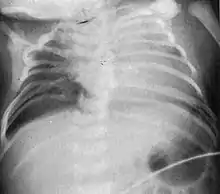

| Radiograph depicting typical skeletal features of Jarcho-Levin syndrome, subtype spondylothoracic dysplasia. Note fanlike configuration of the ribs, with extensive posterior fusion, along with multiple vertebral segmentation defects. | |

Spondylothoracic dysplasia, or STD, has been repeatedly described as an autosomal recessively inherited condition that results in a characteristic fan-like configuration of the ribs with minimal intrinsic rib anomalies. Infants born with this condition typically died early in life due to recurrent respiratory infections and pneumonia due to their restricted thorax.[3][4][5] Recently, a report[6] has documented that actual mortality associated with STD is only about 50%, with many survivors leading healthy, independent lives.